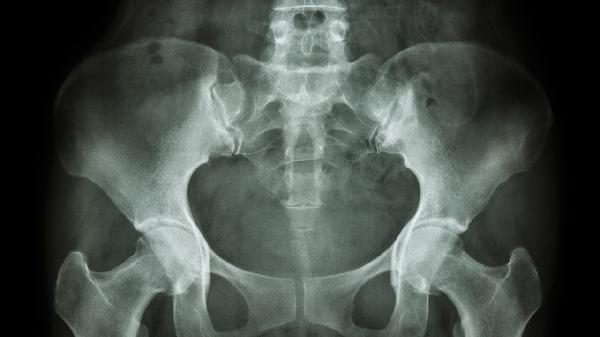

恥骨上膀胱造瘺后應(yīng)注意些什么

恥骨上膀胱造瘺后需注意保持造瘺口清潔、預(yù)防感染、觀察尿液性狀、避免導(dǎo)管受壓或脫落、定期更換造瘺管。造瘺護(hù)理不當(dāng)可能導(dǎo)致尿路感染、導(dǎo)管堵塞或皮膚刺激等并發(fā)癥。